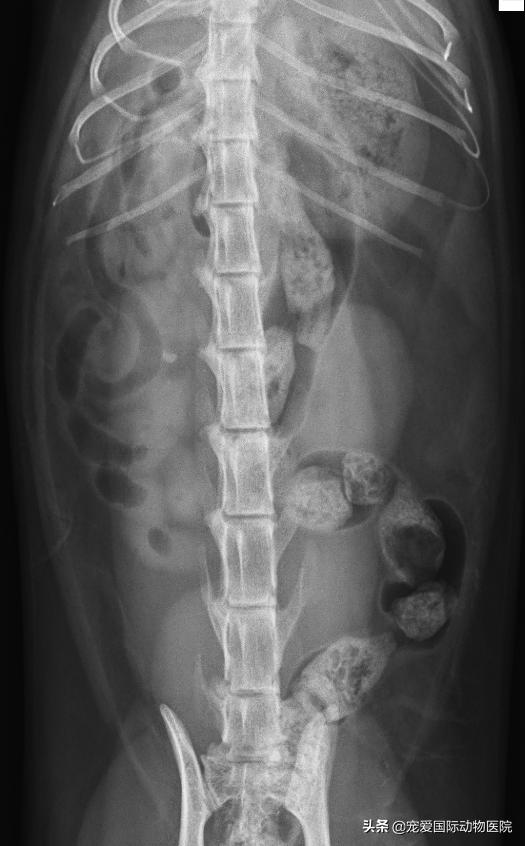

B超检测,见右侧肾盂扩张

内有一直径6MM结石

右侧肾结石,右侧输尿管堵塞

宠爱国际治愈康复的多例肾结石 患宠 !

↑膀胱结石,肾结石,肾衰,肝功异常的小黄,血尿严重,体温36℃,寒颤发抖明显,无食欲,严重脱水,三天的治疗体温37.5,食欲正常,精神状态正常,后天复查,但是其实这些只是指标未治本。

↑猫咪突发尿闭,检查发现不仅有肾结石和膀胱结石,还有严重的肥厚性心肌病。通过治疗,出院定期复查保障身体健康。